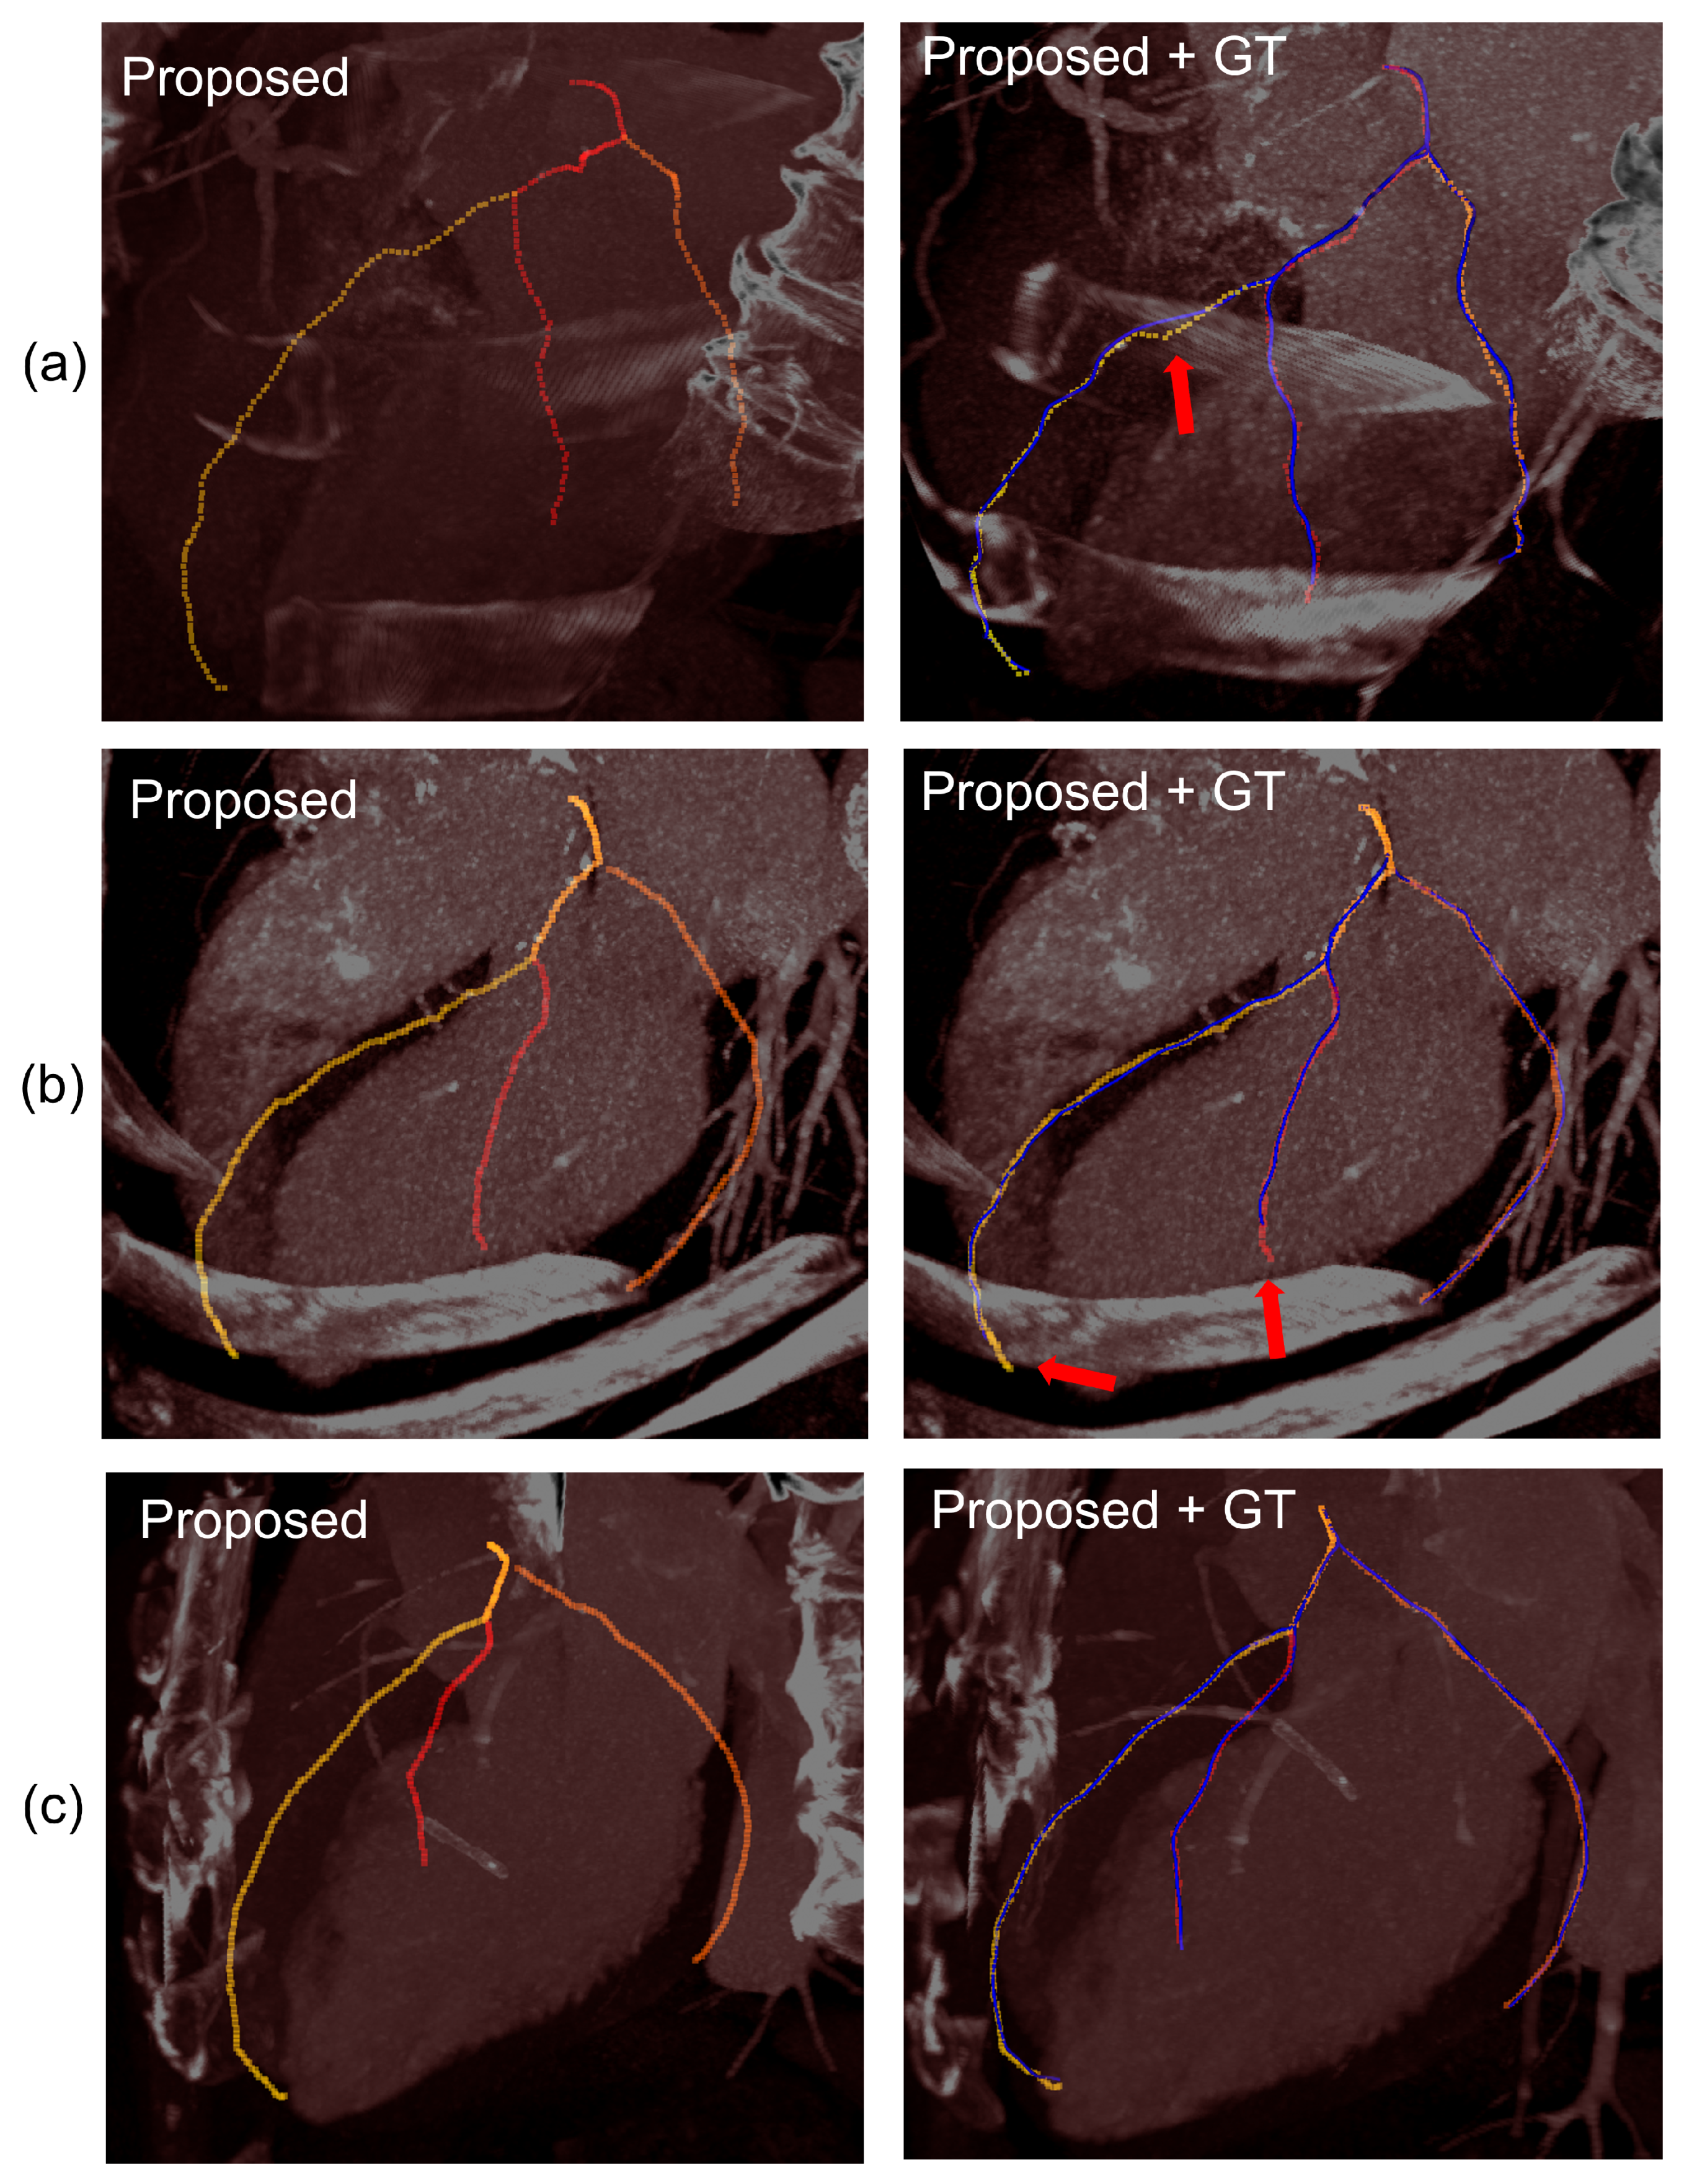

3.3. Evaluation on a CCTA Database

4. Evaluation and Results